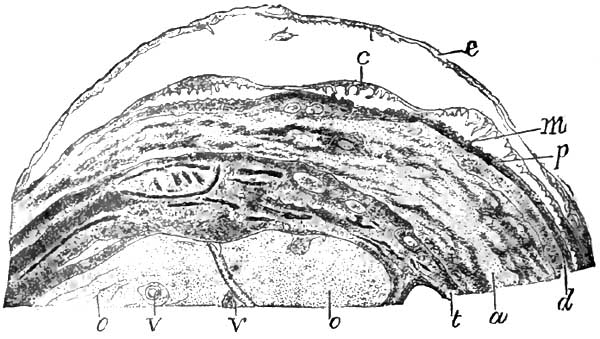

| 6. | PEMPHIGUS BULLA FROM A NEW-BORN SYPHILITIC CHILD |

| 7. | SECTION OF RETE MUCOSUM AND PAPILLÆ FROM SAME CASE OF PEMPHIGUS AS FIG. 6 |